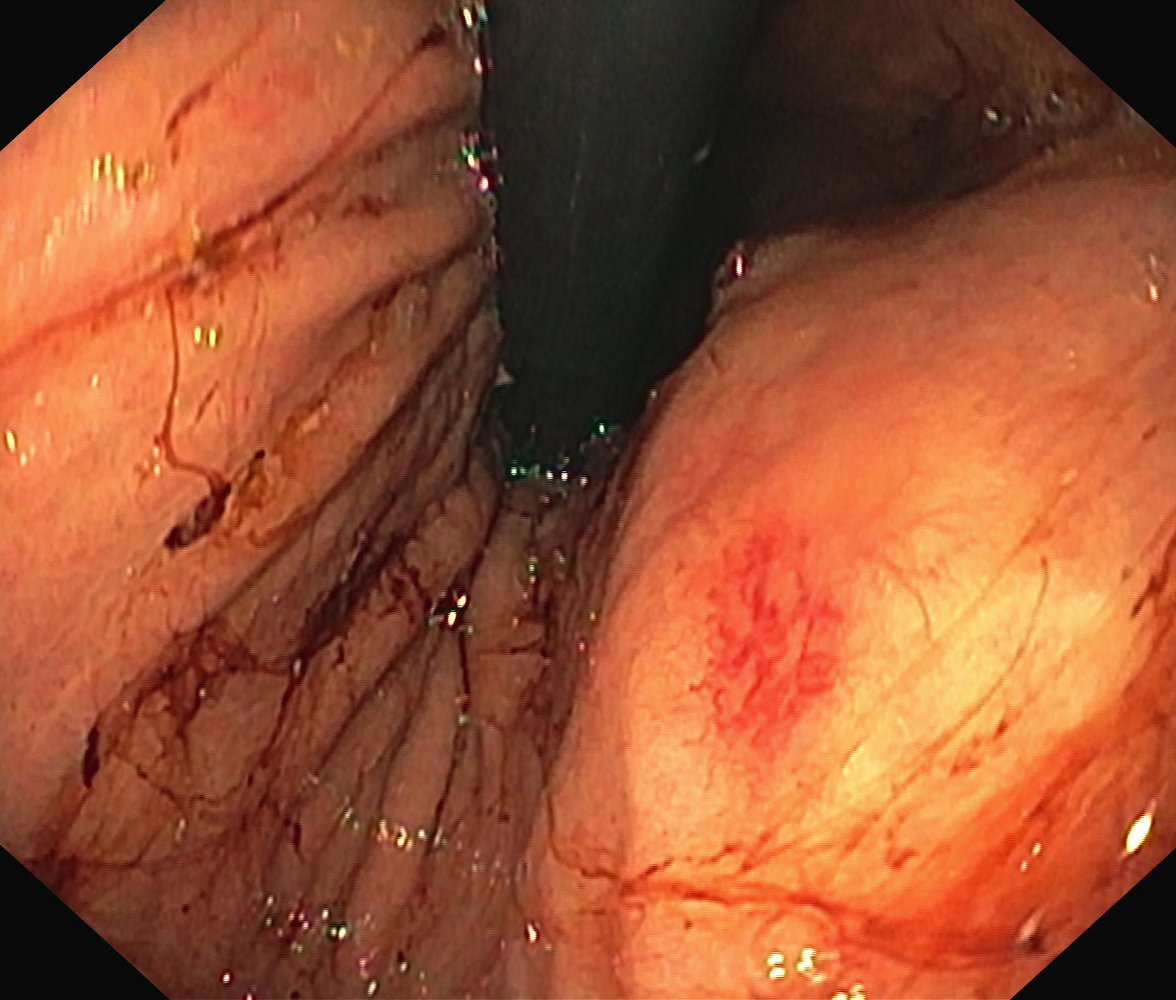

• Findings [2][3]

• Lesion characteristics

• Vessel: flat, cherry-red, and with a fern-like pattern

• Size: < 10 mm

• “Pale halo” sign: a ring of pale mucosa surrounding the angiodysplastic lesion

• The most common locations: colon, duodenum, and jejunum [3]